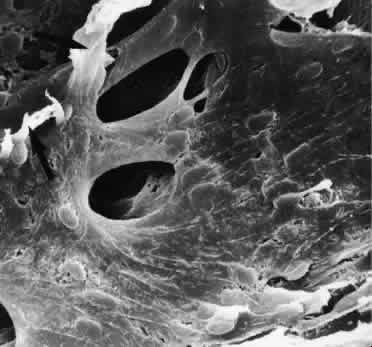

Scanning electron micrographs of serial layers through the entire meshwork and tangential sections (parallel to the inner wall of Schlemm's canal) reveal that the form of the trabecular lamellae and of the intertrabecular spaces changes markedly from the inner to the outer portions of the meshwork. The innermost iridial meshwork consists mostly of long, radial, interconnecting strands forming an irregularly arranged network with rather large openings (Figs. 3 and 4). In the uveal portion, flat sheets are evident that are still relatively irregularly arranged but frequently interconnect with each other. The holes within the uveal meshwork are somewhat smaller than in the iridial meshwork but still show diameters varying between 10 and 30 μm.

Fig. 4. Scanning electron micrograph of the human trabecular meshwork. Internal aspect from the chamber angle side (× 1,640). CE, corneal endothelium; IS, iridial strands (remnants of pectinate ligament); U, uveal meshwork; arrows, corneoscleral meshwork. (Modified from Lütjen-Drecoll E, Rohen JW: Morphology of aqueous outflow pathways in normal and glaucomatous eyes. In Ritch B, Shields MB, Krupin T (eds): The Glaucomas, vol 1, pp 41–74. St. Louis, CV Mosby, 1989)